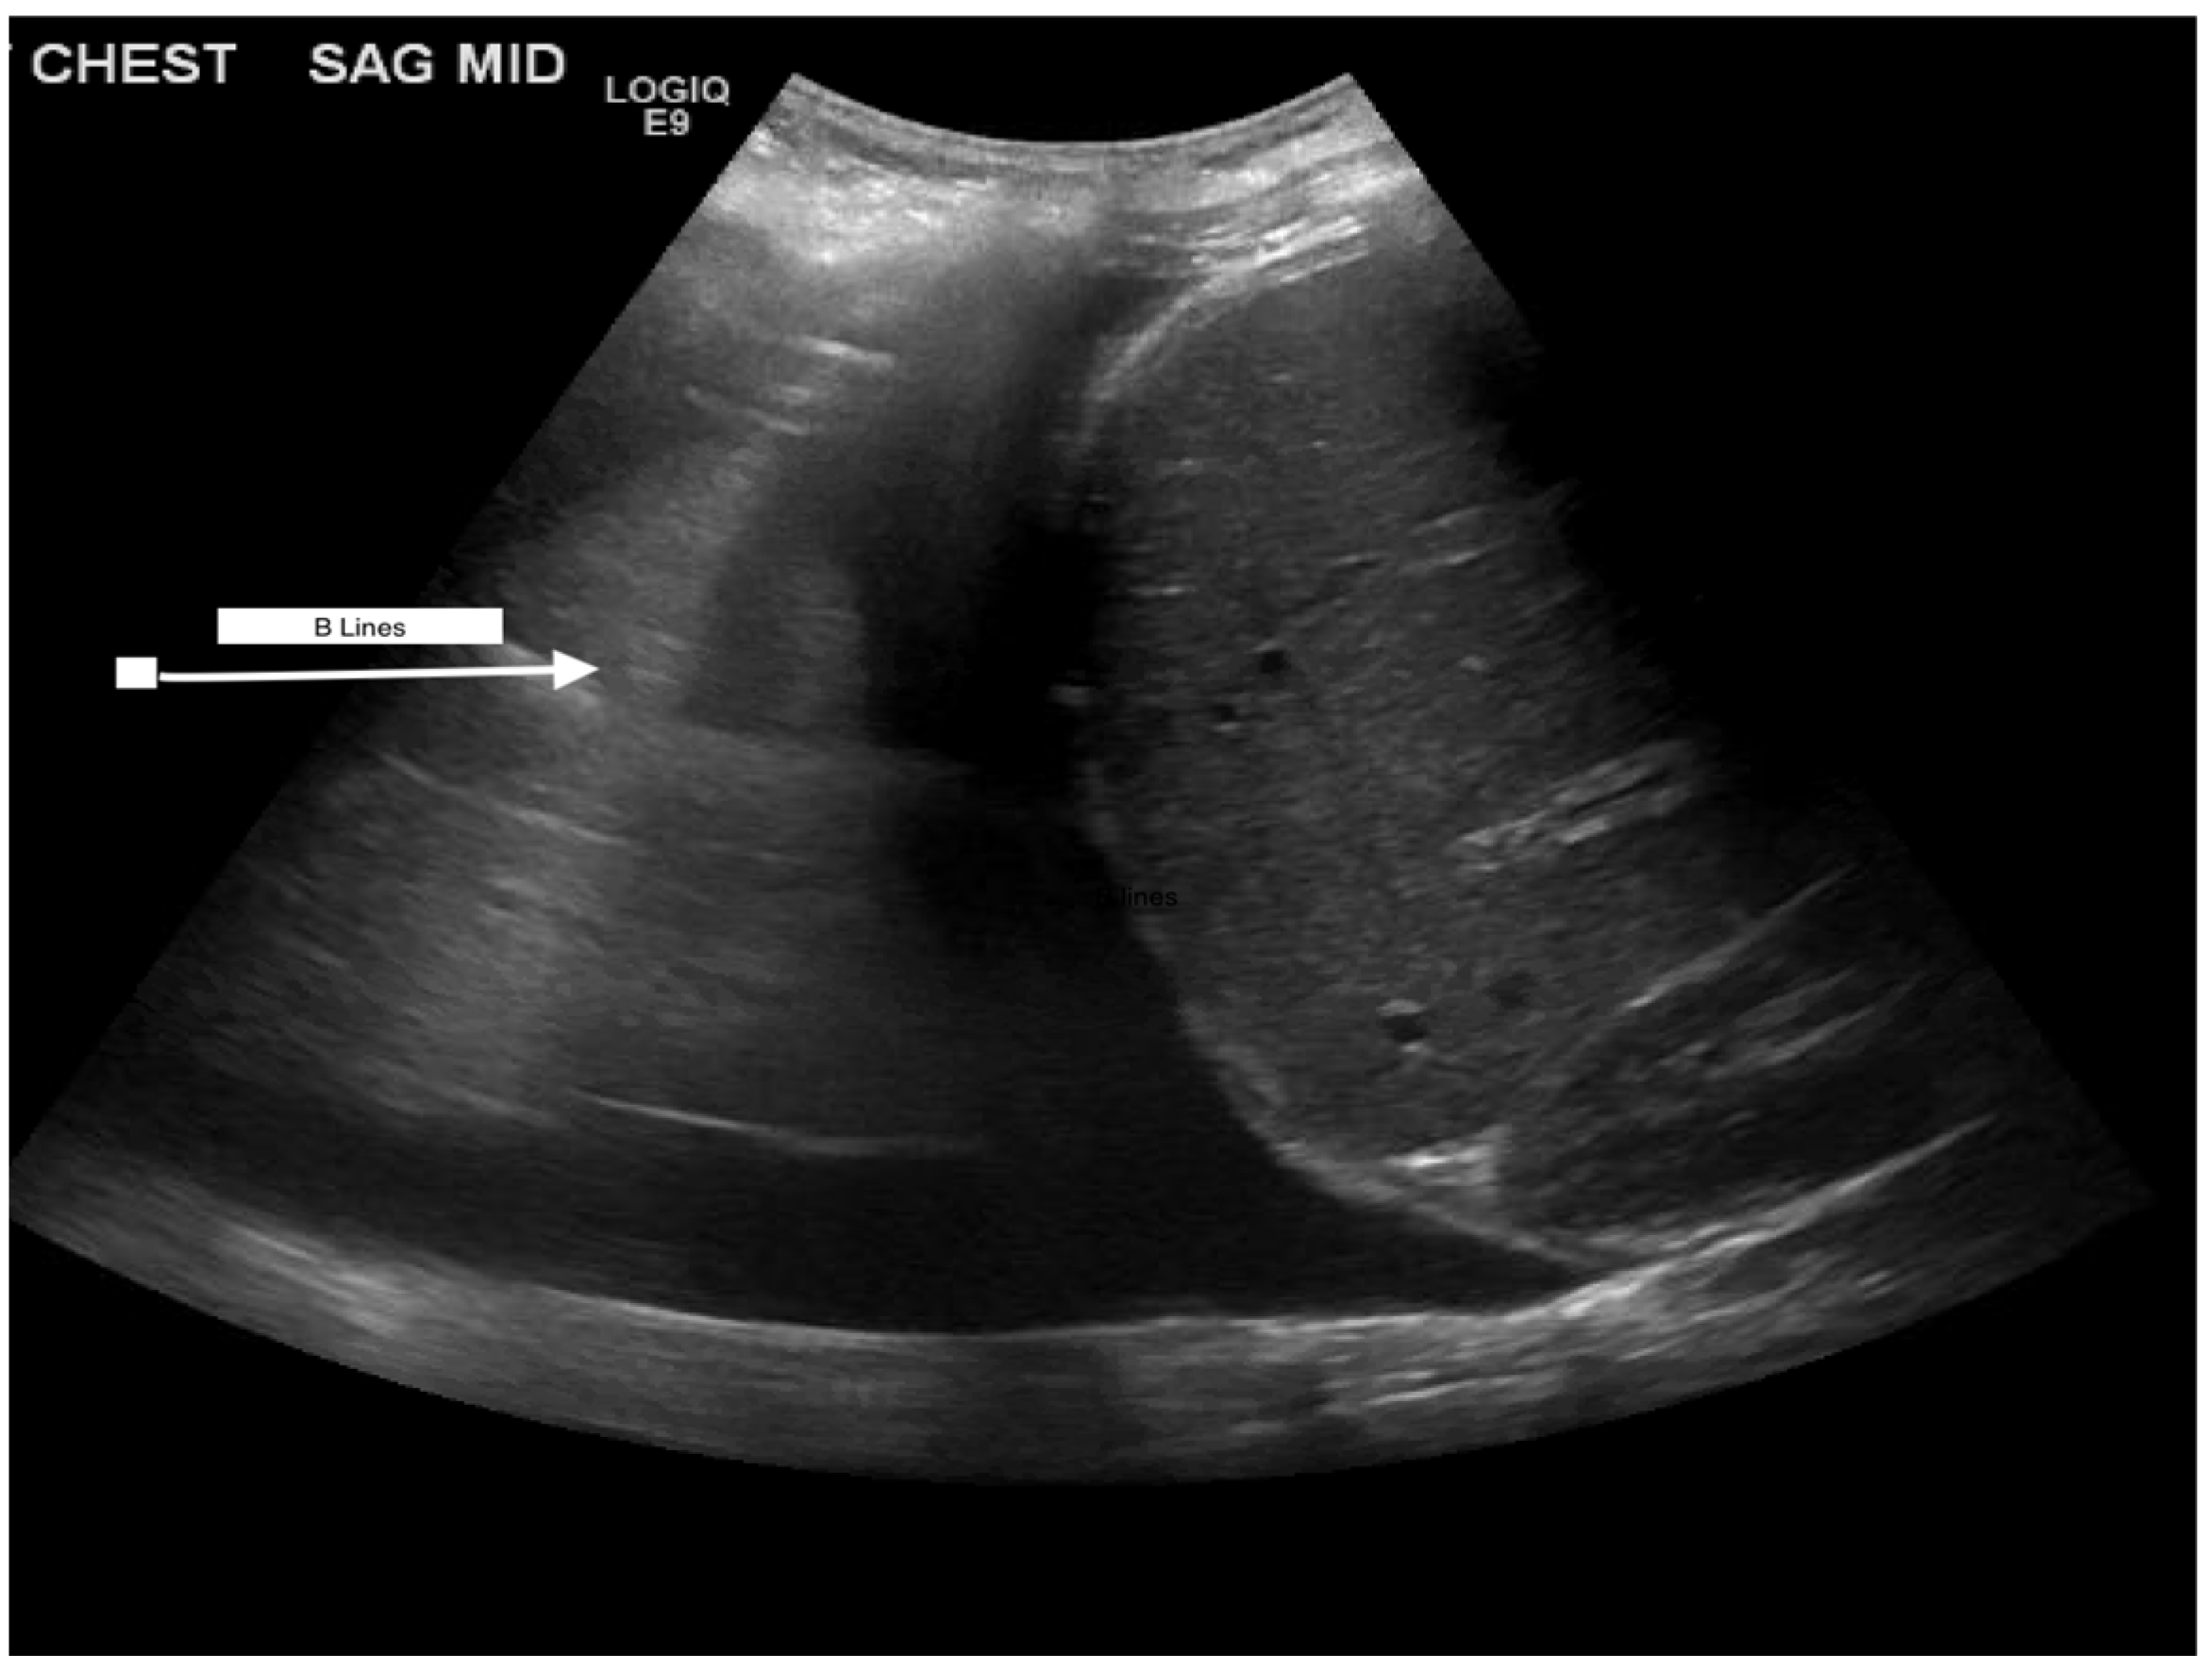

| Venous congestion with Doppler | Diameter > 2 cm indicates congestion in IVC Edema is notable if B-lines present | Requires more evidence | |